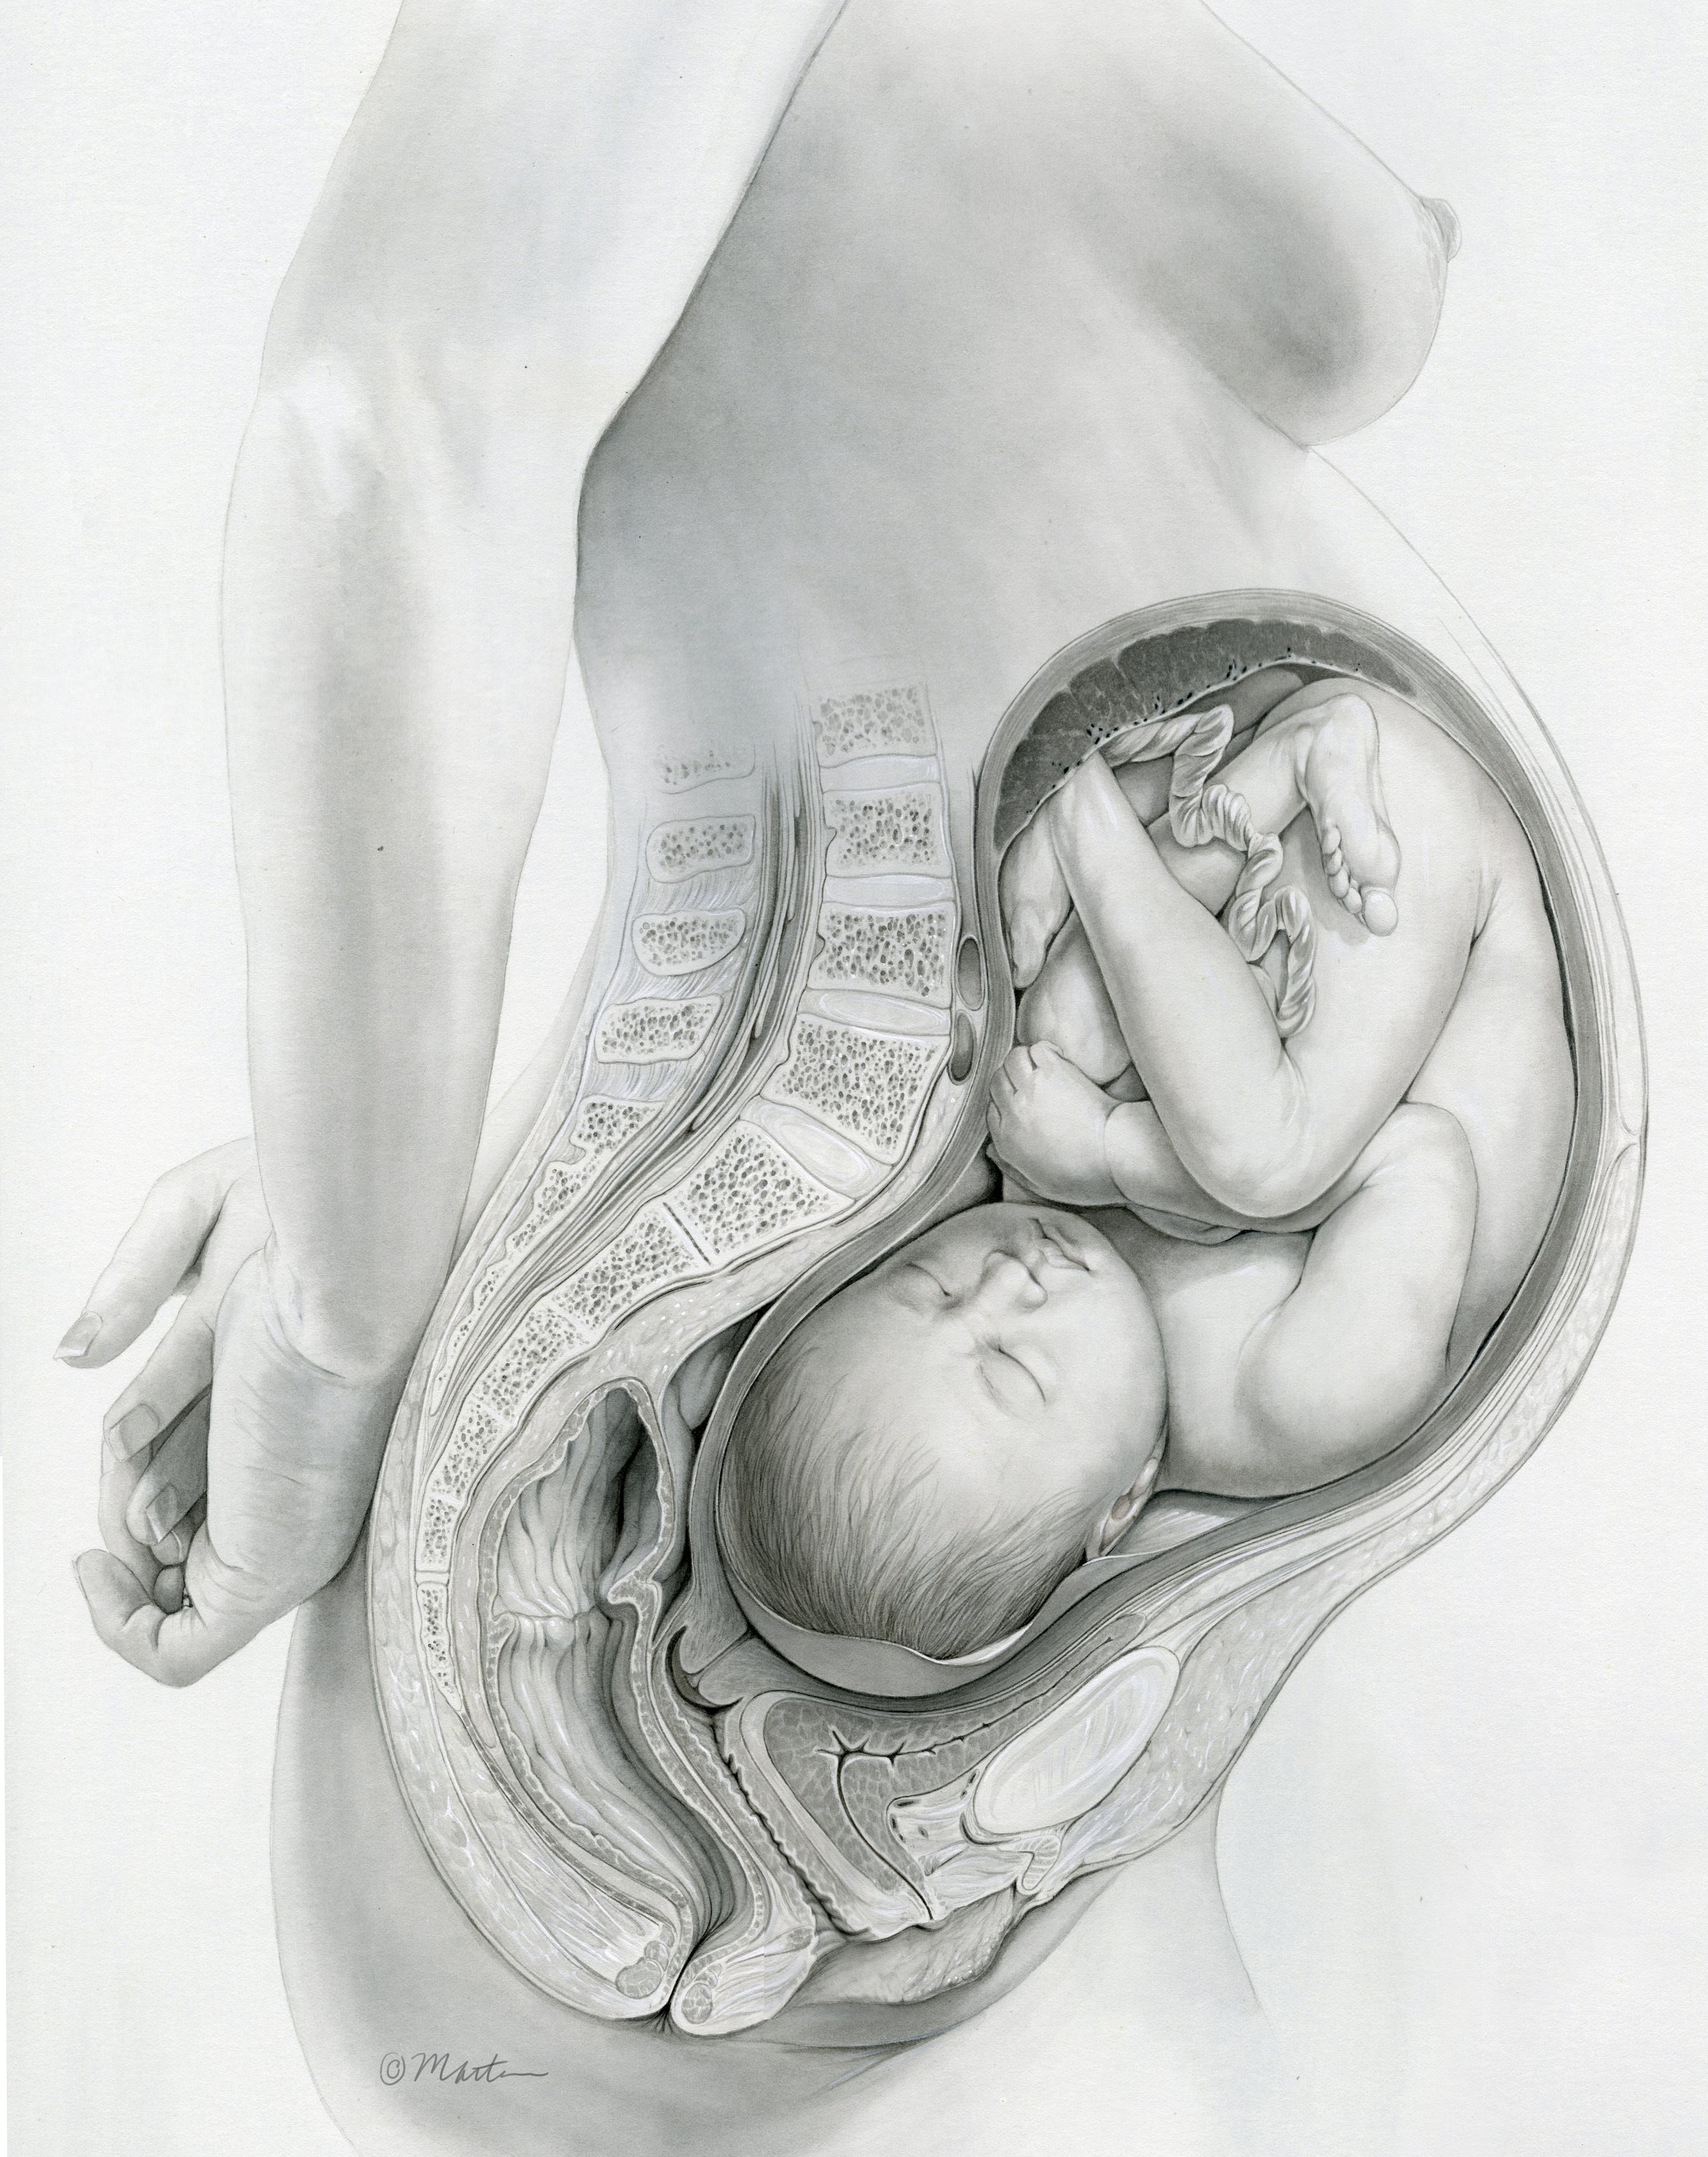

Full Term